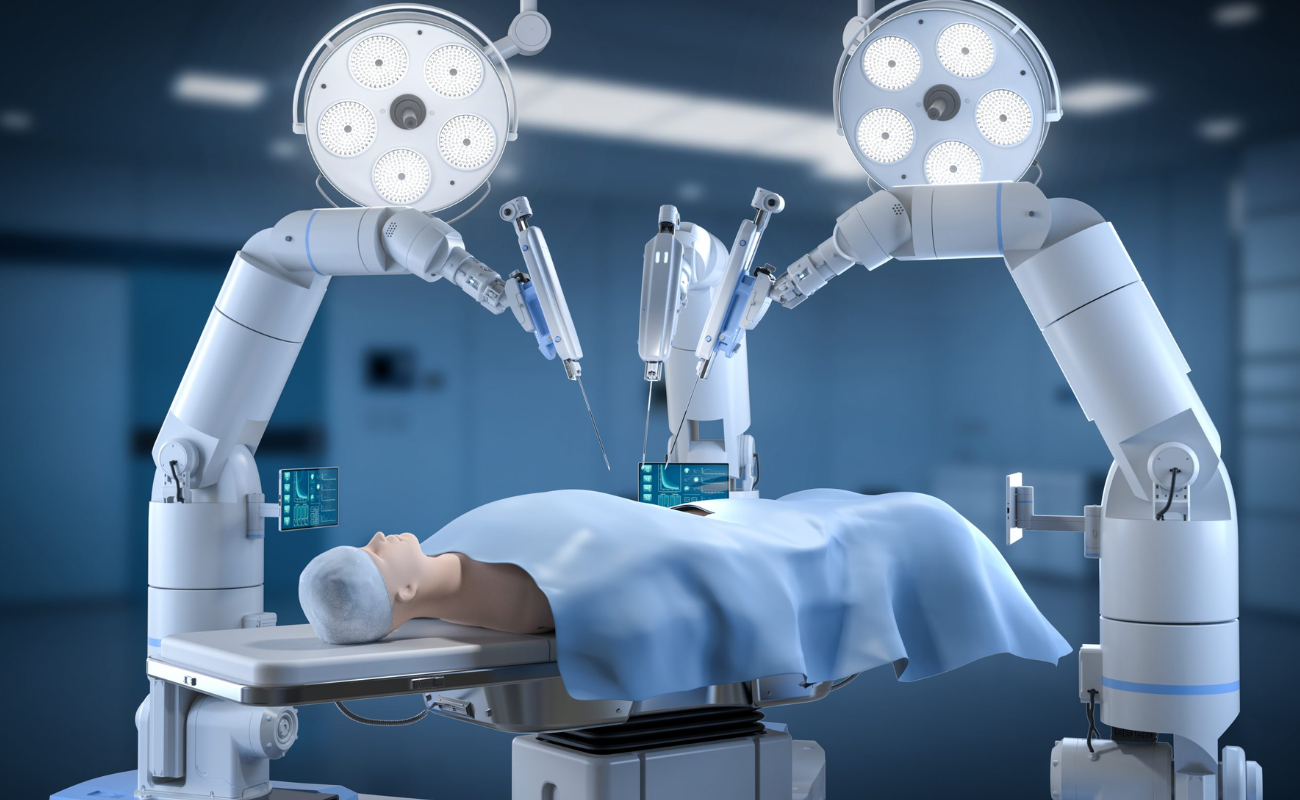

With state-of-the-art robotic joint replacement surgery offering greater accuracy, smaller incisions, and faster recovery times.

The Benefits of Robotic Knee Replacement Surgery

In recent years, medical technology advancements have brought about a revolution in the field of orthopedic surgery, particularly in the realm of knee replacements.

The Impact of Robotics on Knee Replacement: Revolutionizing Orthopedic Surgery

In recent years, orthopedic surgery has undergone a revolutionary transformation through the integration of robotics in knee replacement procedures.

Knee Replacement Surgery: A Comparison of Traditional and Robotic Techniques

When it comes to addressing debilitating knee pain and restoring mobility, knee replacement surgery has been a transformative solution for many individuals.

Transforming Healthcare: Robotic Hip-Replacement Surgery Trends in 2024

In 2024, the healthcare landscape in India is undergoing a remarkable transformation, particularly in the field of orthopedic surgery. Robotic hip-replacement surgery, a revolutionary advancement,

Robotic Surgery: The Future of Healthcare in Chennai

Robotic surgery is revolutionizing healthcare, particularly in Chennai, where advanced medical techniques are becoming increasingly accessible

Chennai Apollo hospital performs 370 robot-assisted orthopedic procedures in 10 months

A robotic knee replacement is just like a traditional knee replacement. The surgeon removes damaged tissue and replaces it with an artificial joint.

Robotic Surgery in Chennai: A Guide for Patients and Caregivers

Robotic surgery is transforming modern healthcare, offering precision, minimally invasive techniques, and faster recovery for patients. As one of the most significant advancements in surgical technology,

What Are the Benefits of Robotic Surgery and Why Do People Choose It?

A surgeon’s hands have been augmented by a machine capable of millimeter-perfect precision. Robotic surgery, a groundbreaking medical innovation that is redefining surgical care around the world, including India. With benefits ranging from minimal

Modern Technology Makes Robotic Surgery Safer Than Ever

In the world of surgery, one technology that has made waves since its introduction is robotic surgery. It has swiftly moved from novelty to necessity in the medical world. Robotic surgery has changed every surgeon’s